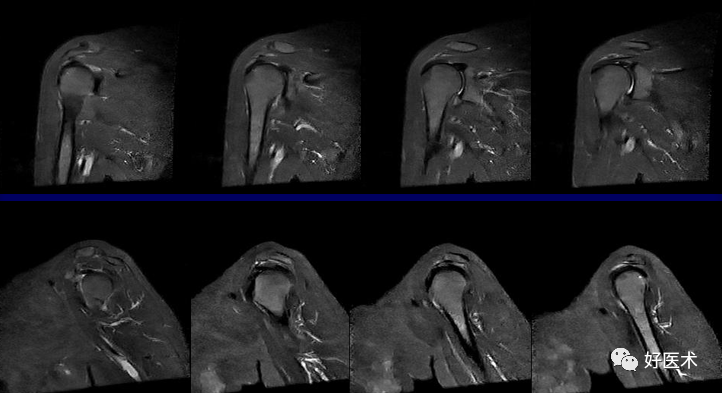

MRI检查技术

(1)体位

仰卧位:检查侧上肢紧贴身体呈中立位或轻度外旋位。

ABER位(前臂外旋外展位):检出关节盂及韧带病变

(2)扫描方位

横轴位:取三维立体定位像的冠状像,扫描层面与关节盂垂直,扫描范围从肩峰至肱骨颈下。

斜冠状位:取横断位作定位像,扫描层面与冈上肌腱平行,扫描范围为锁骨外端至肩峰。

斜矢状位:取横断位作定位像,扫描层面与关节盂平行,扫描范围包括肱骨头和整个关节盂。

轴位:评估Bankart lesions 和盂唇损伤、评估肩胛下肌肌腱。

斜冠状、斜矢状:显示肩袖及冈上肌走行、显示喙肩弓。

斜冠状、轴位:评估盂唇撕裂、肱二头肌长头腱与上盂唇的连接。

轴位:显示肩胛下肌腱撕裂、盂唇撕裂

冠状位:显示肩袖撕裂、盂唇撕裂

矢状位:显示肩袖撕裂、盂唇撕裂